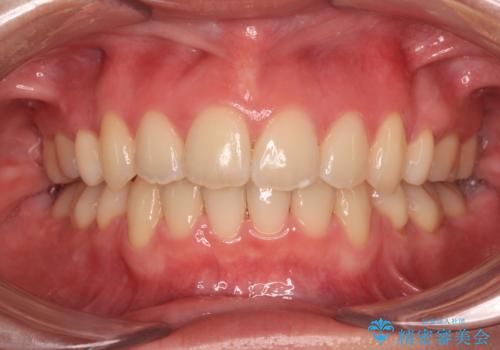

- 前歯2本が飛び出してることを気にして来院された患者様です。

全体的に黄ばんだ歯の色も気になるとのことで、マウスピース矯正により飛び出した前歯を治しつつ、ホームホワイトニングを併用して黄ばみを解消していくこととしました。

歯と歯の間を削ることで、飛び出した前歯が引っ込み、スッキリとした口元となりました。

歯の黄ばみも改善され、明るい歯並びとなりました。